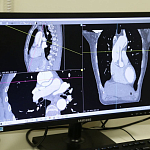

19 декабря поступил мужчина с острым расслоением аорты. В его случае риск летального исхода составлял 90%. Во время операции было принято решение заменить значительную часть аорты на специальный протез. Также была применена и другая новая технология: на 40 минут полностью остановили кровоснабжение всего организма, кроме головного мозга.

Врач – анестезиолог-реаниматолог отделения анестезиологии и реанимации с палатами реанимации и интенсивной терапии № 2 Керим Зияддинов в данной операции оказал помощь перфузиолога – проводил искусственное кровообращение. Врач отмечает, что столь острая патология с таким типом расслоения аорты оперировалась в Крыму впервые.